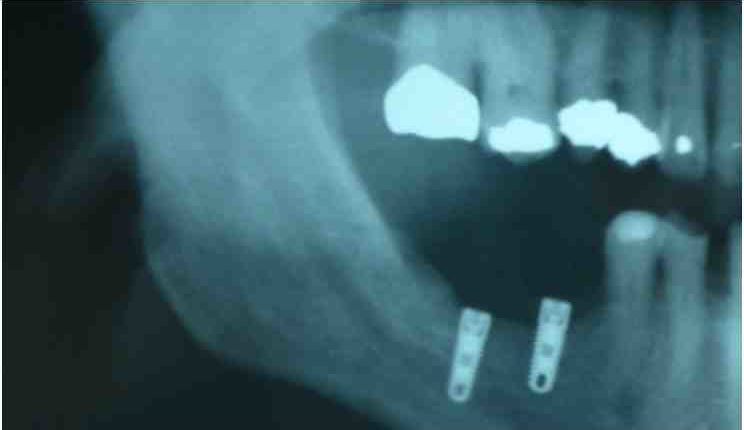

Can you use TENS over metal?

Unlike short wave diathermy, it does not contraindicate the use of electrical stimulation over metal (ie, compression screws, metal plates, wires, joint replacements). An electrical stimulus brought to a tingling sensation for pain reduction is appropriate following an open reduction external fixation.